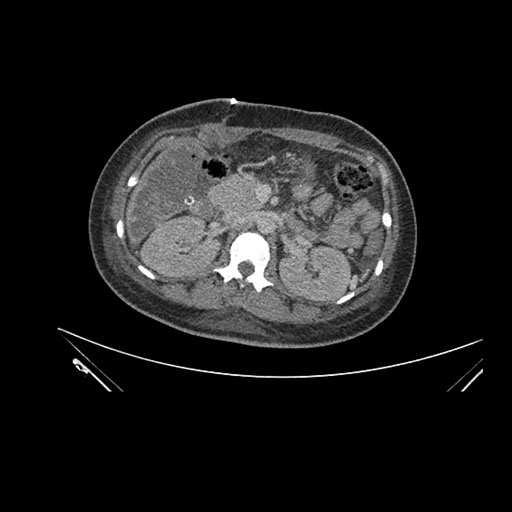

Imaging Analysis

Look through the patient's CT scan to identify any areas of concern for the necessary procedure.

Axial Venous

Based on initial findings, which issue(s) would you be most concerned about?